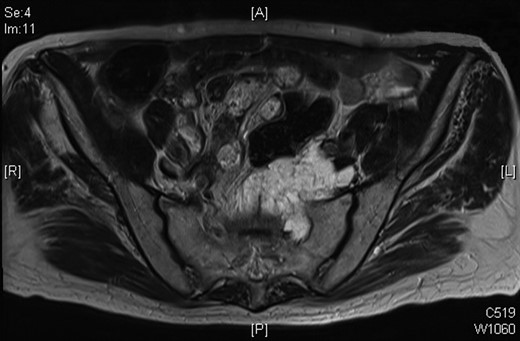

In October 2009, a magnetic resonance imaging (MRI) scan of his spine was arranged due to leg pain thought to be of neurological origin. This did, indeed, showed marked L5 and S1 spinal stenosis; however, it also showed an irregular mass in the left side of the pelvis anterior to the sacrum and abutting the distal rectum and the emerging left S1 nerve root on the anterior surface of the sacrum. Overall, the dimensions were 3.6 × 4.3 × 3.8 cm. There was a similar area of soft tissue on the previous CT of September 2008. The possibility of a further slow-growing rectal recurrence was raised. This was discussed at multidisciplinary team meeting and as the mass was cold on PET scan in March 2009, it was decided to repeat the PET scan, which was done in February 2010 and November 2010, and the mass again showed no uptake.

In July 2012, a follow-up MRI was done as surveillance for the mass, and this showed that the mass had extended into the left S1 neural foramen and another similar high signal area was seen to the left of the lower rectum and his CEA has continued to rise. After much discussion and in view of age and co-morbidity, together with the involvement of the pelvic sidewall, an R0 resection was not possible.

MRI scan of 2009 showing a mucinous mass in the left side of the pelvis below the anastomosis from his original sigmoid colectomy.

Progression of the mucinous mass on MRI in 2012. On repeated PET scanning, the mass shows minimal cellular activity.